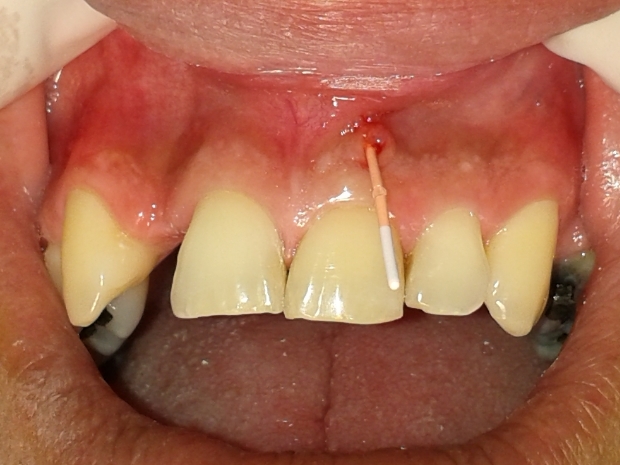

O mesmo relatava histórico de trauma dental na infância, sendo que previamente foi submetido a uma intervenção de urgência no elemento 21 por outro profissional, visto que se apresentava com edema e dor na região apical. Pela presença de fístula nesta região, foi realizado rastreamento na mesma, sendo a mesma oriunda do elemento dental 21 (figuras 2 e 3).

- Figura 2

- Figura 3